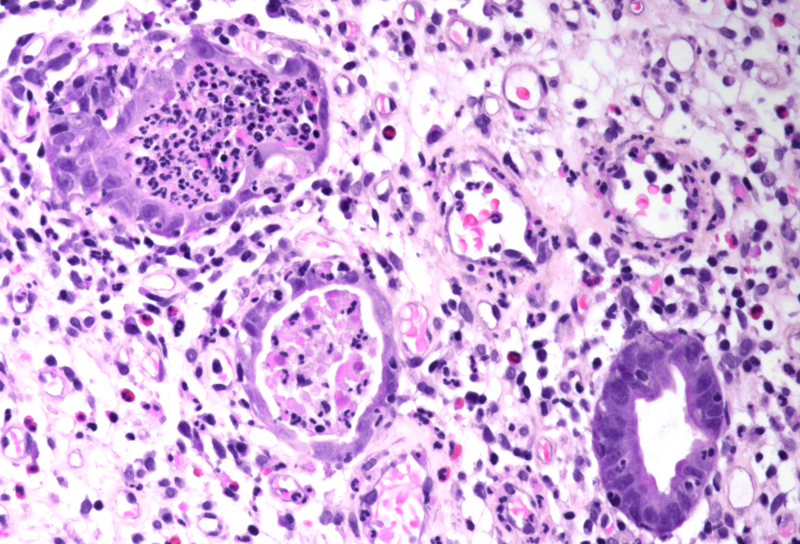

Gastric biopsies from a 68-year-old male with history of lung cancer.

Immune checkpoint inhibitor associated gastritis.

Histology showed an extremely altered gastric mucosa, with architectural distortion by glandular atrophy, degenerative epithelial changes, erosions and an expanded oedematous lamina propria (PANEL A-C). On higher magnification, the lamina propria contained a mixed inflammatory infiltrate, characterized by lymphocytes, plasma cells, eosinophils and neutrophils, focally with abscess formation. We observed withering glands lined by flattened eosinophilic epithelium, occasionally containing apoptotic debris (PANEL D-E); in other areas, little atrophic neuroendocrine nests were found (PANEL F). In summary, there was a severe acute inflammation and signs of acute epithelial injury highly suggestive of a drug-induced gastritis, consistent with injury due to pembrolizumab.